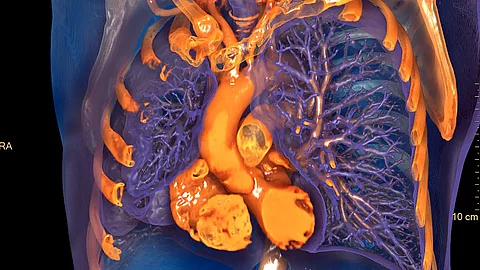

Zum Funktionsumfang von IntelliSpace Portal 12 gehört außerdem ein neues Tool für das fotorealistische Volume Rendering.7 Mit einer virtuellen, frei beweglichen Lichtquelle lassen sich bestimmte Bereiche gezielt illuminieren und die Plastizität der 3D-Strukturen verstärken.

7 Das fotorealistische Volume Rendering von IntelliSpace Portal ist nicht für die Befundung geeignet.